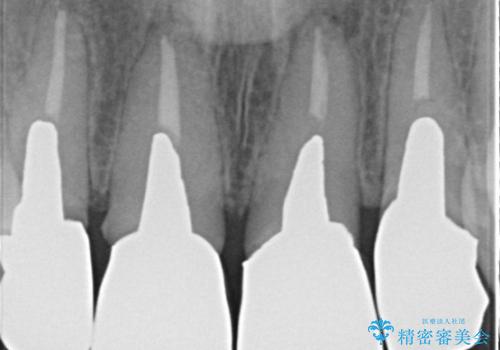

- 歯ぐきの黒っぽさ、暗い色調の前歯の改善を求めて来院されました。

金属を用いたコア・クラウンが装着されており、全ての金属を除去したのちのメタルフリー治療を計画します。

金属のフレームを用いるクラウンは色調が暗くなる傾向にありますが、セラミッククラウンに置き換えたことで自然な明るさ、審美性を取り戻すことができました。